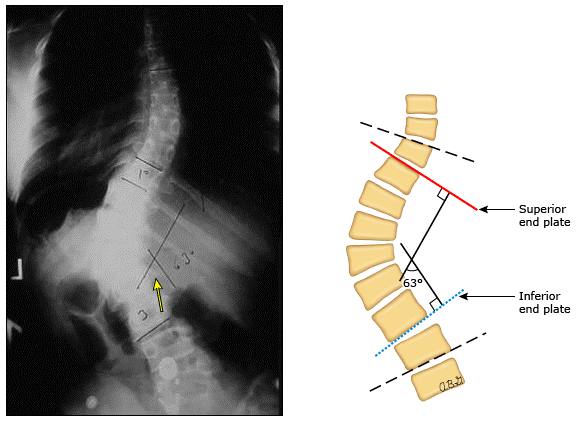

Cobb角测量法。按照惯例,以弯曲≥10°来界定脊柱侧凸。Cobb角<10°的弯曲在脊柱不对称的正常范围内,这种弯曲并无远期临床意义。

Cobb角≥70°患者可能存在限制性肺疾病; Cobb角≥40°患者39%存在阻塞性肺疾病。